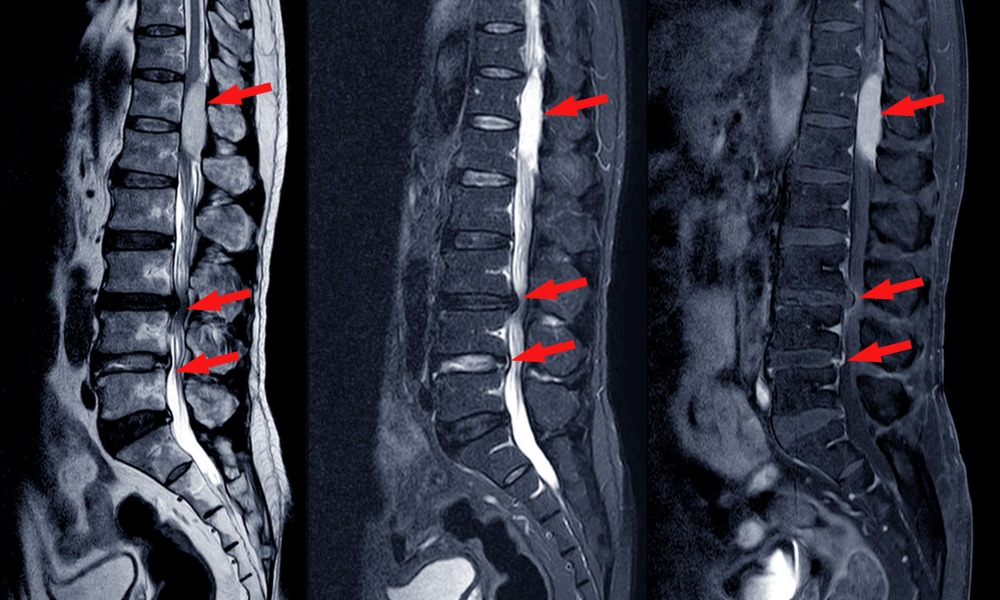

Degenerative Disc Disease

What is Degenerative Disc Disease? Degenerative disc disease is not a disease at all but a term to describe the...

In its most basic definition, a bulging or herniated disc occurs when an intervertebral disc, which serves as a cushion...

Learn MoreHerniated Discs

A herniated disc is a condition in which the outer shell of a cushion between the vertebrae in the spine...

Learn MoreSpinal Stenosis

Spinal stenosis refers to a condition typically found only in adults over the age of 50 in which the spinal...